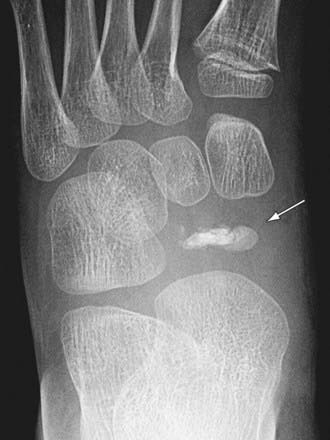

Osteochondroses are acquired focal disorders of ossification involving epiphyses, apophyses, and other epiphyseal equivalents. Idiopathic avascular necrosis is rarely observed in the tarsal navicular (Köhler disease) or the 2nd or 3rd metatarsal head (Freiberg infraction). Köhler disease (Fig. 666-7) typically appears in children around age 5 or 6 yr and is 3-fold more common in boys than girls. Freiberg infraction is more common in girls and typically occur between ages 8 and 17 yr. Thess are generally self-limited conditions that commonly result in activity-related pain, which can at times be disabling. The treatment is based on the degree of symptoms and commonly includes restriction of activity. For patients with Köhler disease, a short leg cast (6-8 wk) can provide significant relief. Patients with Freiberg infraction can benefit from a period of casting and/or shoe modifications such as a rocker-bottom sole, a stiff-soled shoe, or a metatarsal bar. Degenerative changes occasionally occur following the gradual healing process, and surgical intervention is required in a subset of cases. Procedures have included joint debridement, bone grafting, redirectional osteotomy, subtotal or complete excision of the metatarsal head, and joint replacement.

image

Figure 666-7 Köhler disease. Anteroposterior radiograph of a 7 yr old boy who presented with fever, pain, and swelling of the midfoot. The left foot reveals a small, fragmented, sclerotic navicular (arrow).

(From Slovis TL, editor: Caffey’s pediatric diagnostic imaging, ed 11, vol 2, Philadelphia, 2008, Mosby.)